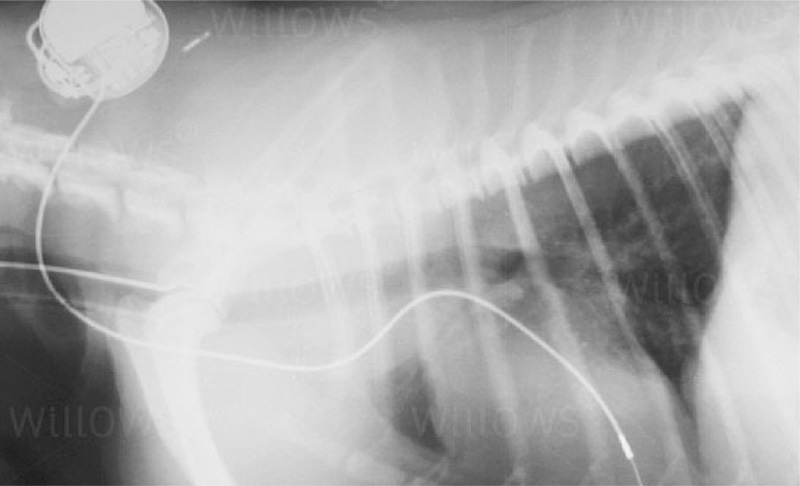

A xray of a pacemaker implantation showing the lead coursing from the heart up the cranial vena cava to the jugular vein and then subcutaneously back to the generator.

In dogs the pacemaker is inserted under the skin at the side of the neck. A pacing lead connects the pacemaker to the heart and delivers the electrical ‘spark’ that creates the heartbeat. Before recommending pacemaker implantation, our Cardiologists will check the medical history provided by your Vet as well as the results of any diagnostic tests such as bloodwork, ECG and chest x-rays. They will also perform a thorough clinical examination and cardiac ultrasound scan to check for any underlying problems.